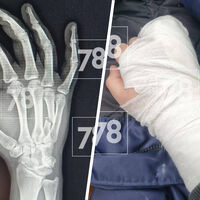

Врачу диагностировали закрытую черепно-мозговую травму и закрытый перелом правой кисти.